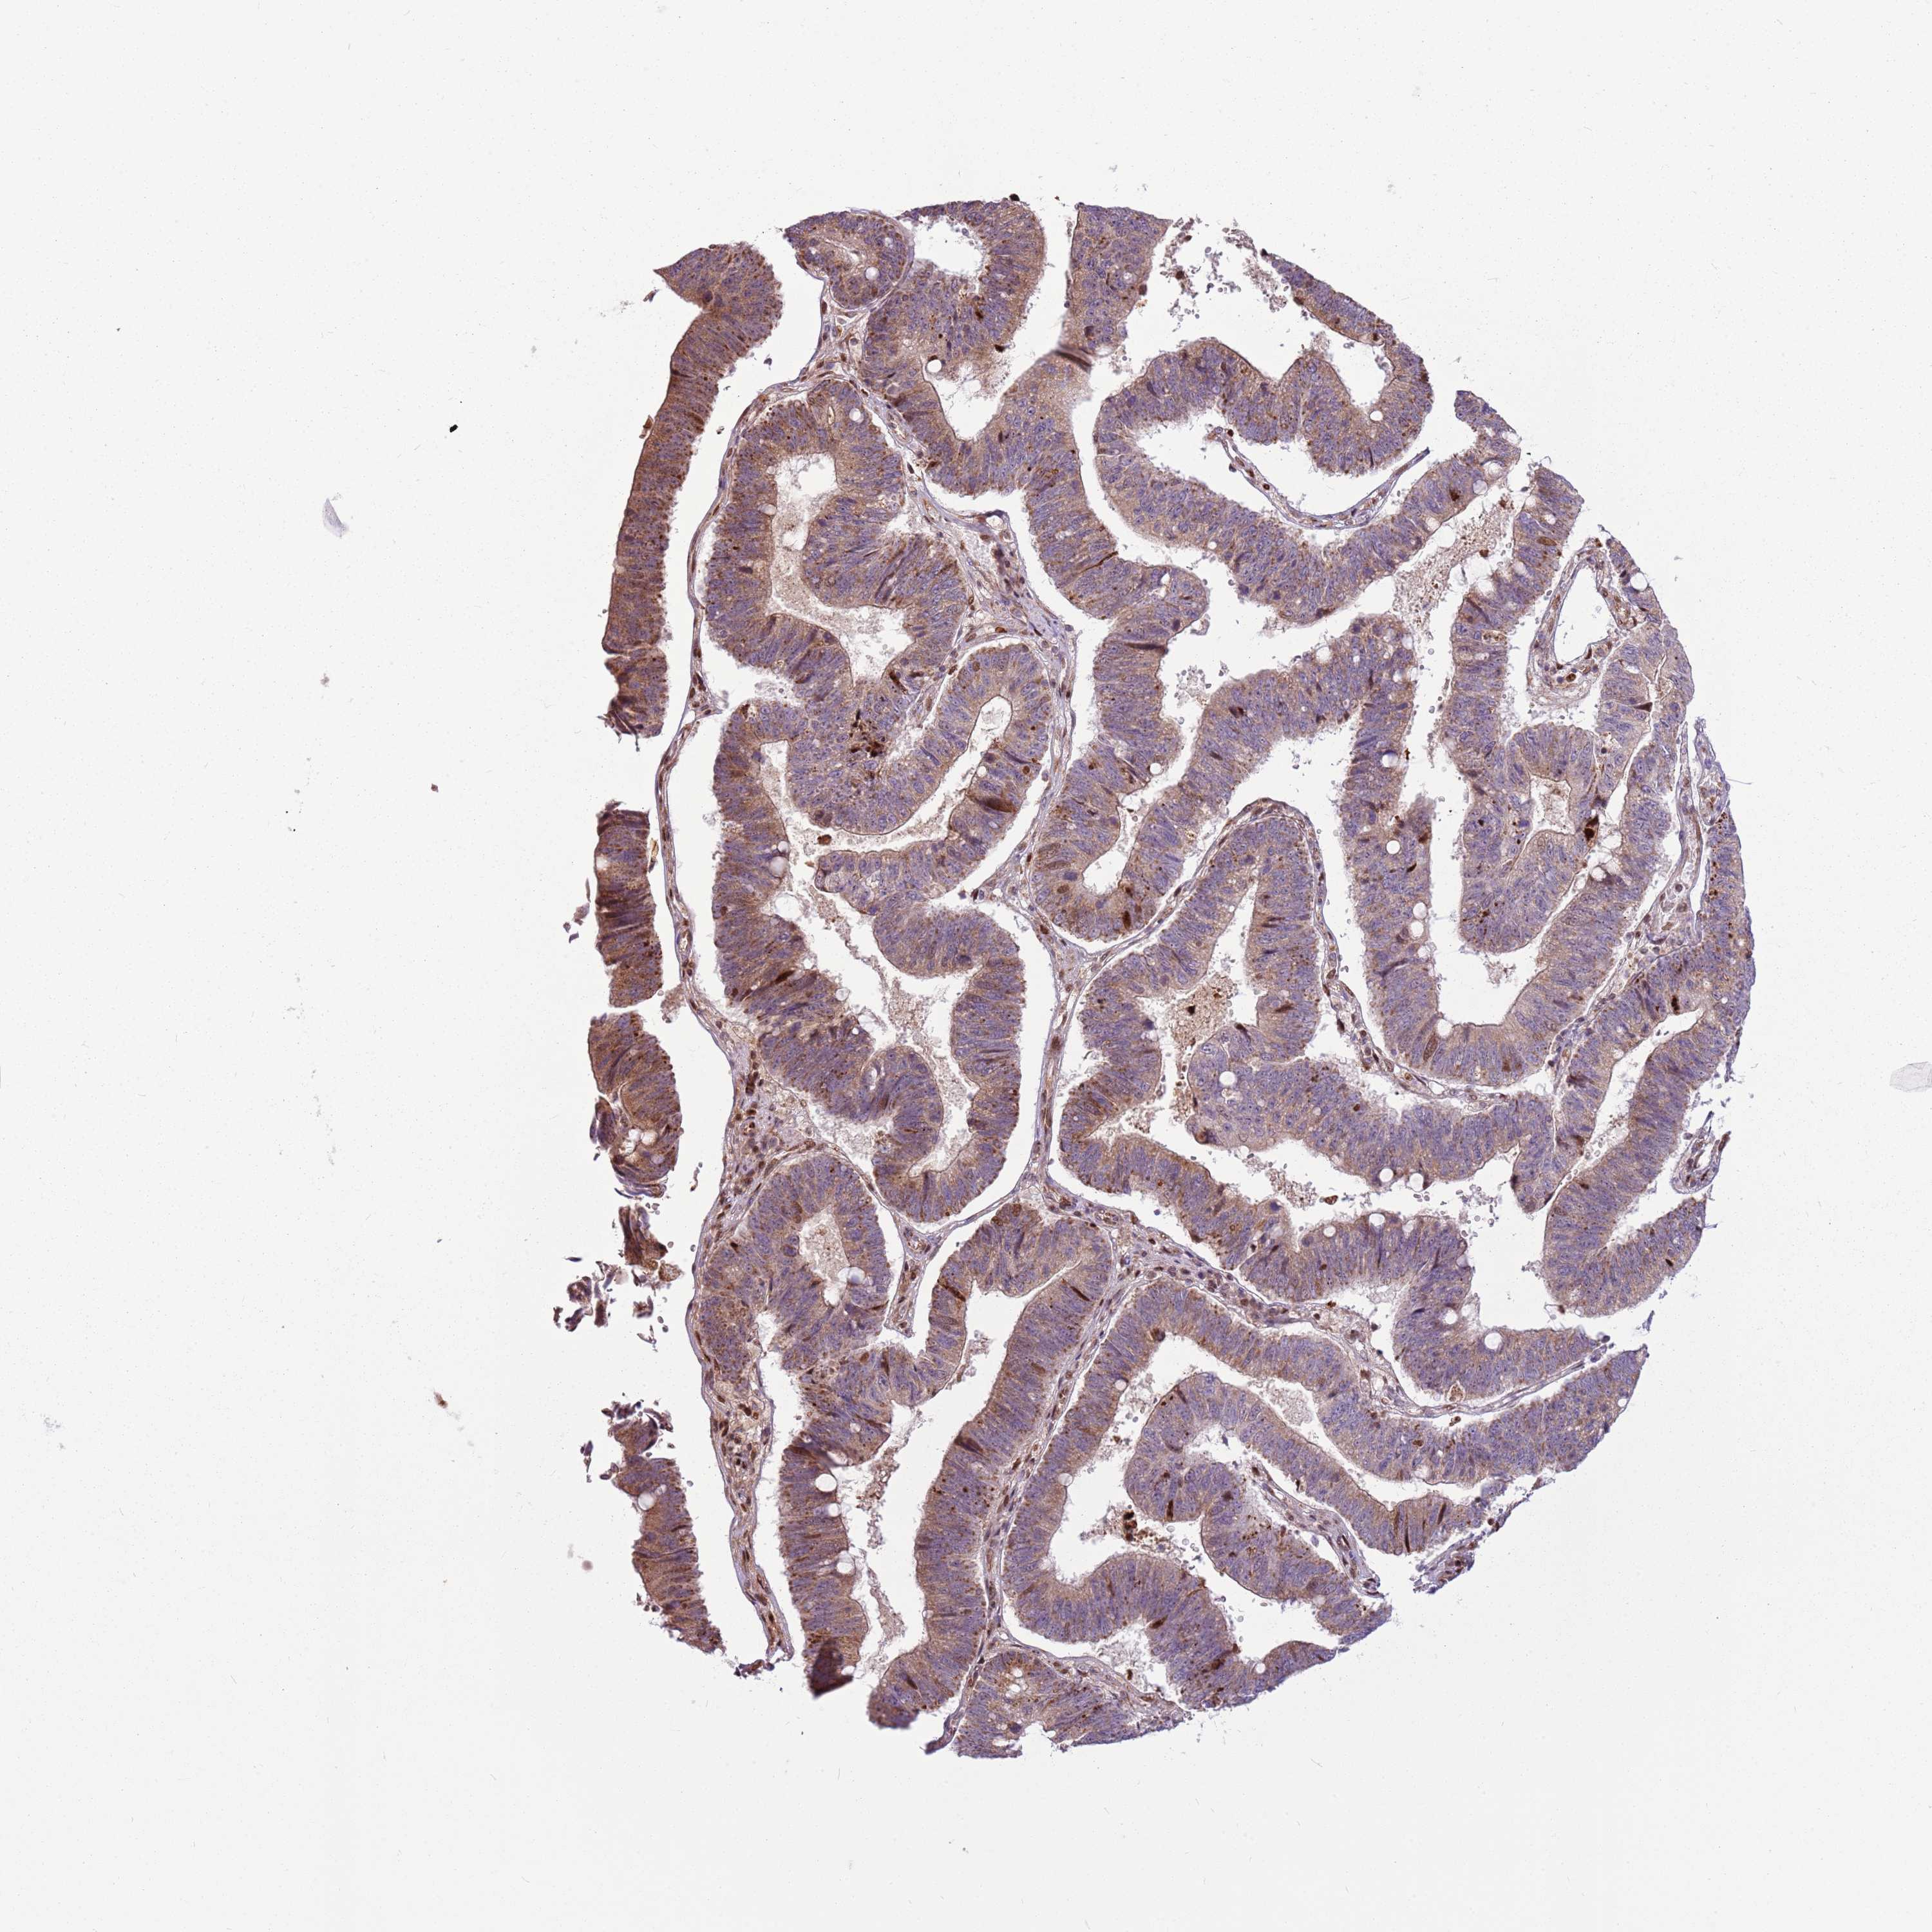

STOMACH CANCER - Protein expressioni

A mouse-over function shows sample information and annotation data. Click on an image to view it in a full screen mode. Samples can be filtered based on level of antibody staining by selecting one or several of the following categories: high, medium, low and not detected. The assay and annotation is described here.

Note that samples used for immunohistochemistry by the Human Protein Atlas do not correspond to samples in the TCGA dataset.

Antibody stainingi

Antibody staining in the annotated cell types in the current human tissue is reported as not detected, low, medium, or high, based on conventional immunohistochemistry profiling in selected tissues. This score is based on the combination of the staining intensity and fraction of stained cells.

Each image is clickable and will lead to virtual microscopy that enables deeper exploration of all samples and also displays staining intensity scores, fraction scores and subcellular localization as well as patient and tissue information for each sample.

Antibody HPA022979

Staining

High

Medium

Low

Not detected

Intensity

Strong

Moderate

Weak

Negative

Quantity

>75%

75%-25%

<25%

None

Location

Nuclear

Cytoplasmic/membranous

Cytoplasmic/membranous,nuclear

Adenocarcinoma, NOS